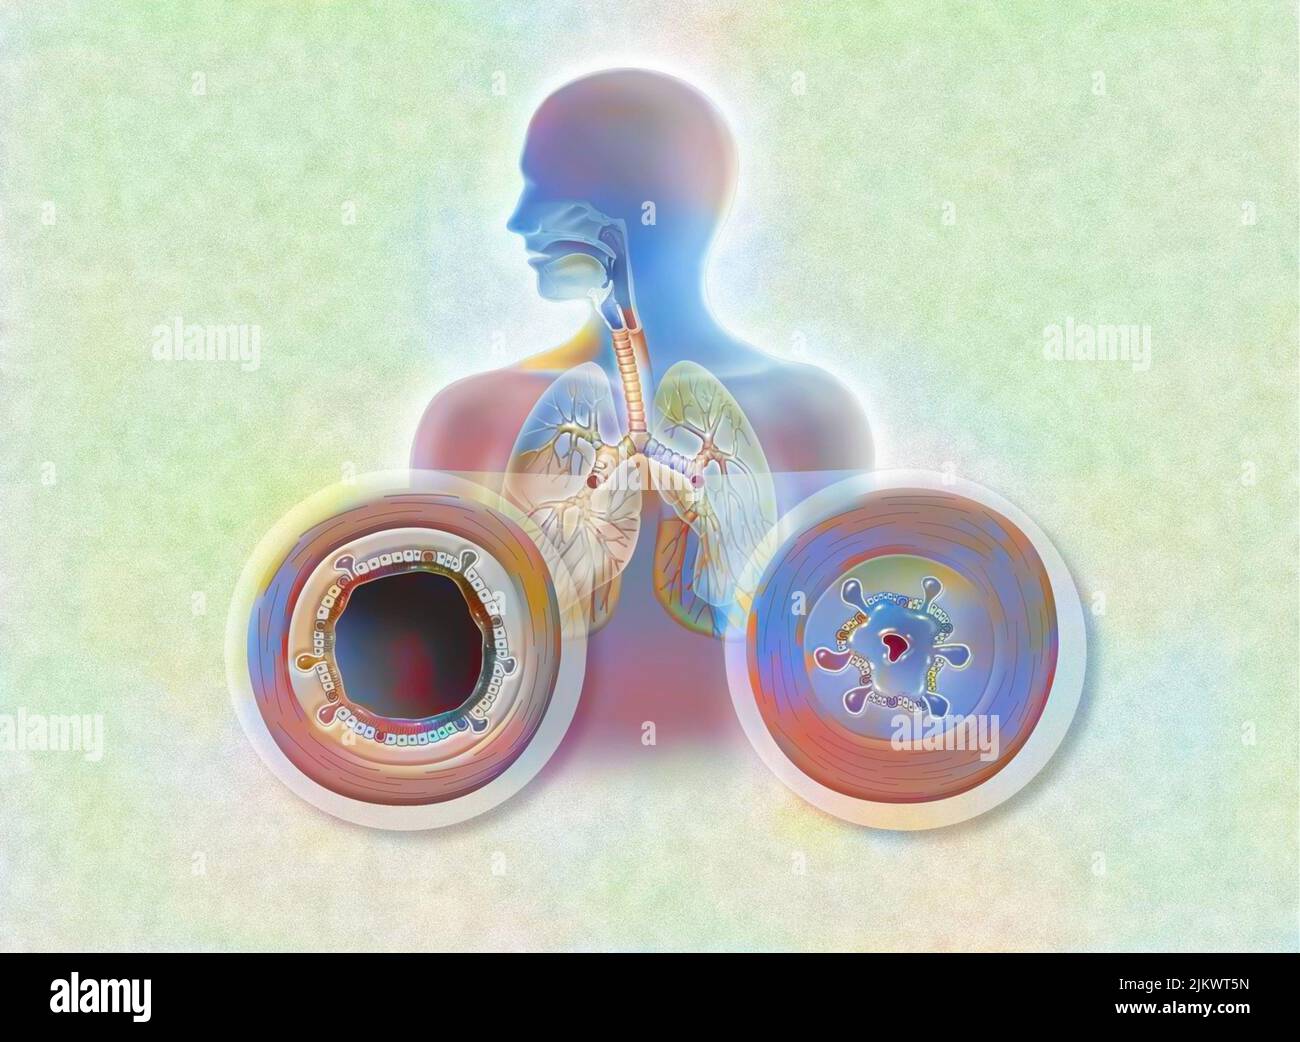

Effect of the bronchodilator on a bronchus with an asthma attack (left) and COPD (right). Stock Photohttps://www.alamy.com/image-license-details/?v=1https://www.alamy.com/effect-of-the-bronchodilator-on-a-bronchus-with-an-asthma-attack-left-and-copd-right-image476926507.html

Effect of the bronchodilator on a bronchus with an asthma attack (left) and COPD (right). Stock Photohttps://www.alamy.com/image-license-details/?v=1https://www.alamy.com/effect-of-the-bronchodilator-on-a-bronchus-with-an-asthma-attack-left-and-copd-right-image476926507.htmlRF2JKWTHF–Effect of the bronchodilator on a bronchus with an asthma attack (left) and COPD (right).

Bronchodilator on a bronchus with an asthma attack and COPD. Stock Photohttps://www.alamy.com/image-license-details/?v=1https://www.alamy.com/bronchodilator-on-a-bronchus-with-an-asthma-attack-and-copd-image476923686.html

Bronchodilator on a bronchus with an asthma attack and COPD. Stock Photohttps://www.alamy.com/image-license-details/?v=1https://www.alamy.com/bronchodilator-on-a-bronchus-with-an-asthma-attack-and-copd-image476923686.htmlRF2JKWN0P–Bronchodilator on a bronchus with an asthma attack and COPD.

Effect of the bronchodilator on a bronchus with an asthma attack (left) and COPD (right). Stock Photohttps://www.alamy.com/image-license-details/?v=1https://www.alamy.com/effect-of-the-bronchodilator-on-a-bronchus-with-an-asthma-attack-left-and-copd-right-image476926523.html

Effect of the bronchodilator on a bronchus with an asthma attack (left) and COPD (right). Stock Photohttps://www.alamy.com/image-license-details/?v=1https://www.alamy.com/effect-of-the-bronchodilator-on-a-bronchus-with-an-asthma-attack-left-and-copd-right-image476926523.htmlRF2JKWTJ3–Effect of the bronchodilator on a bronchus with an asthma attack (left) and COPD (right).

Bronchodilator on a bronchus with an asthma attack and COPD. Stock Photohttps://www.alamy.com/image-license-details/?v=1https://www.alamy.com/bronchodilator-on-a-bronchus-with-an-asthma-attack-and-copd-image476923650.html

Bronchodilator on a bronchus with an asthma attack and COPD. Stock Photohttps://www.alamy.com/image-license-details/?v=1https://www.alamy.com/bronchodilator-on-a-bronchus-with-an-asthma-attack-and-copd-image476923650.htmlRF2JKWMYE–Bronchodilator on a bronchus with an asthma attack and COPD.